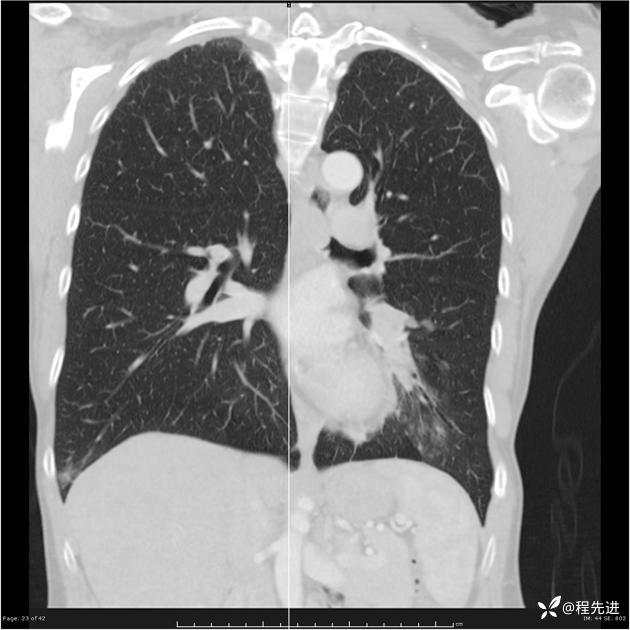

病例女,53岁,气管、左主支气管、下叶支气管内结节,乳头状瘤?期待你的精彩解读

女,53岁

乳头状瘤?